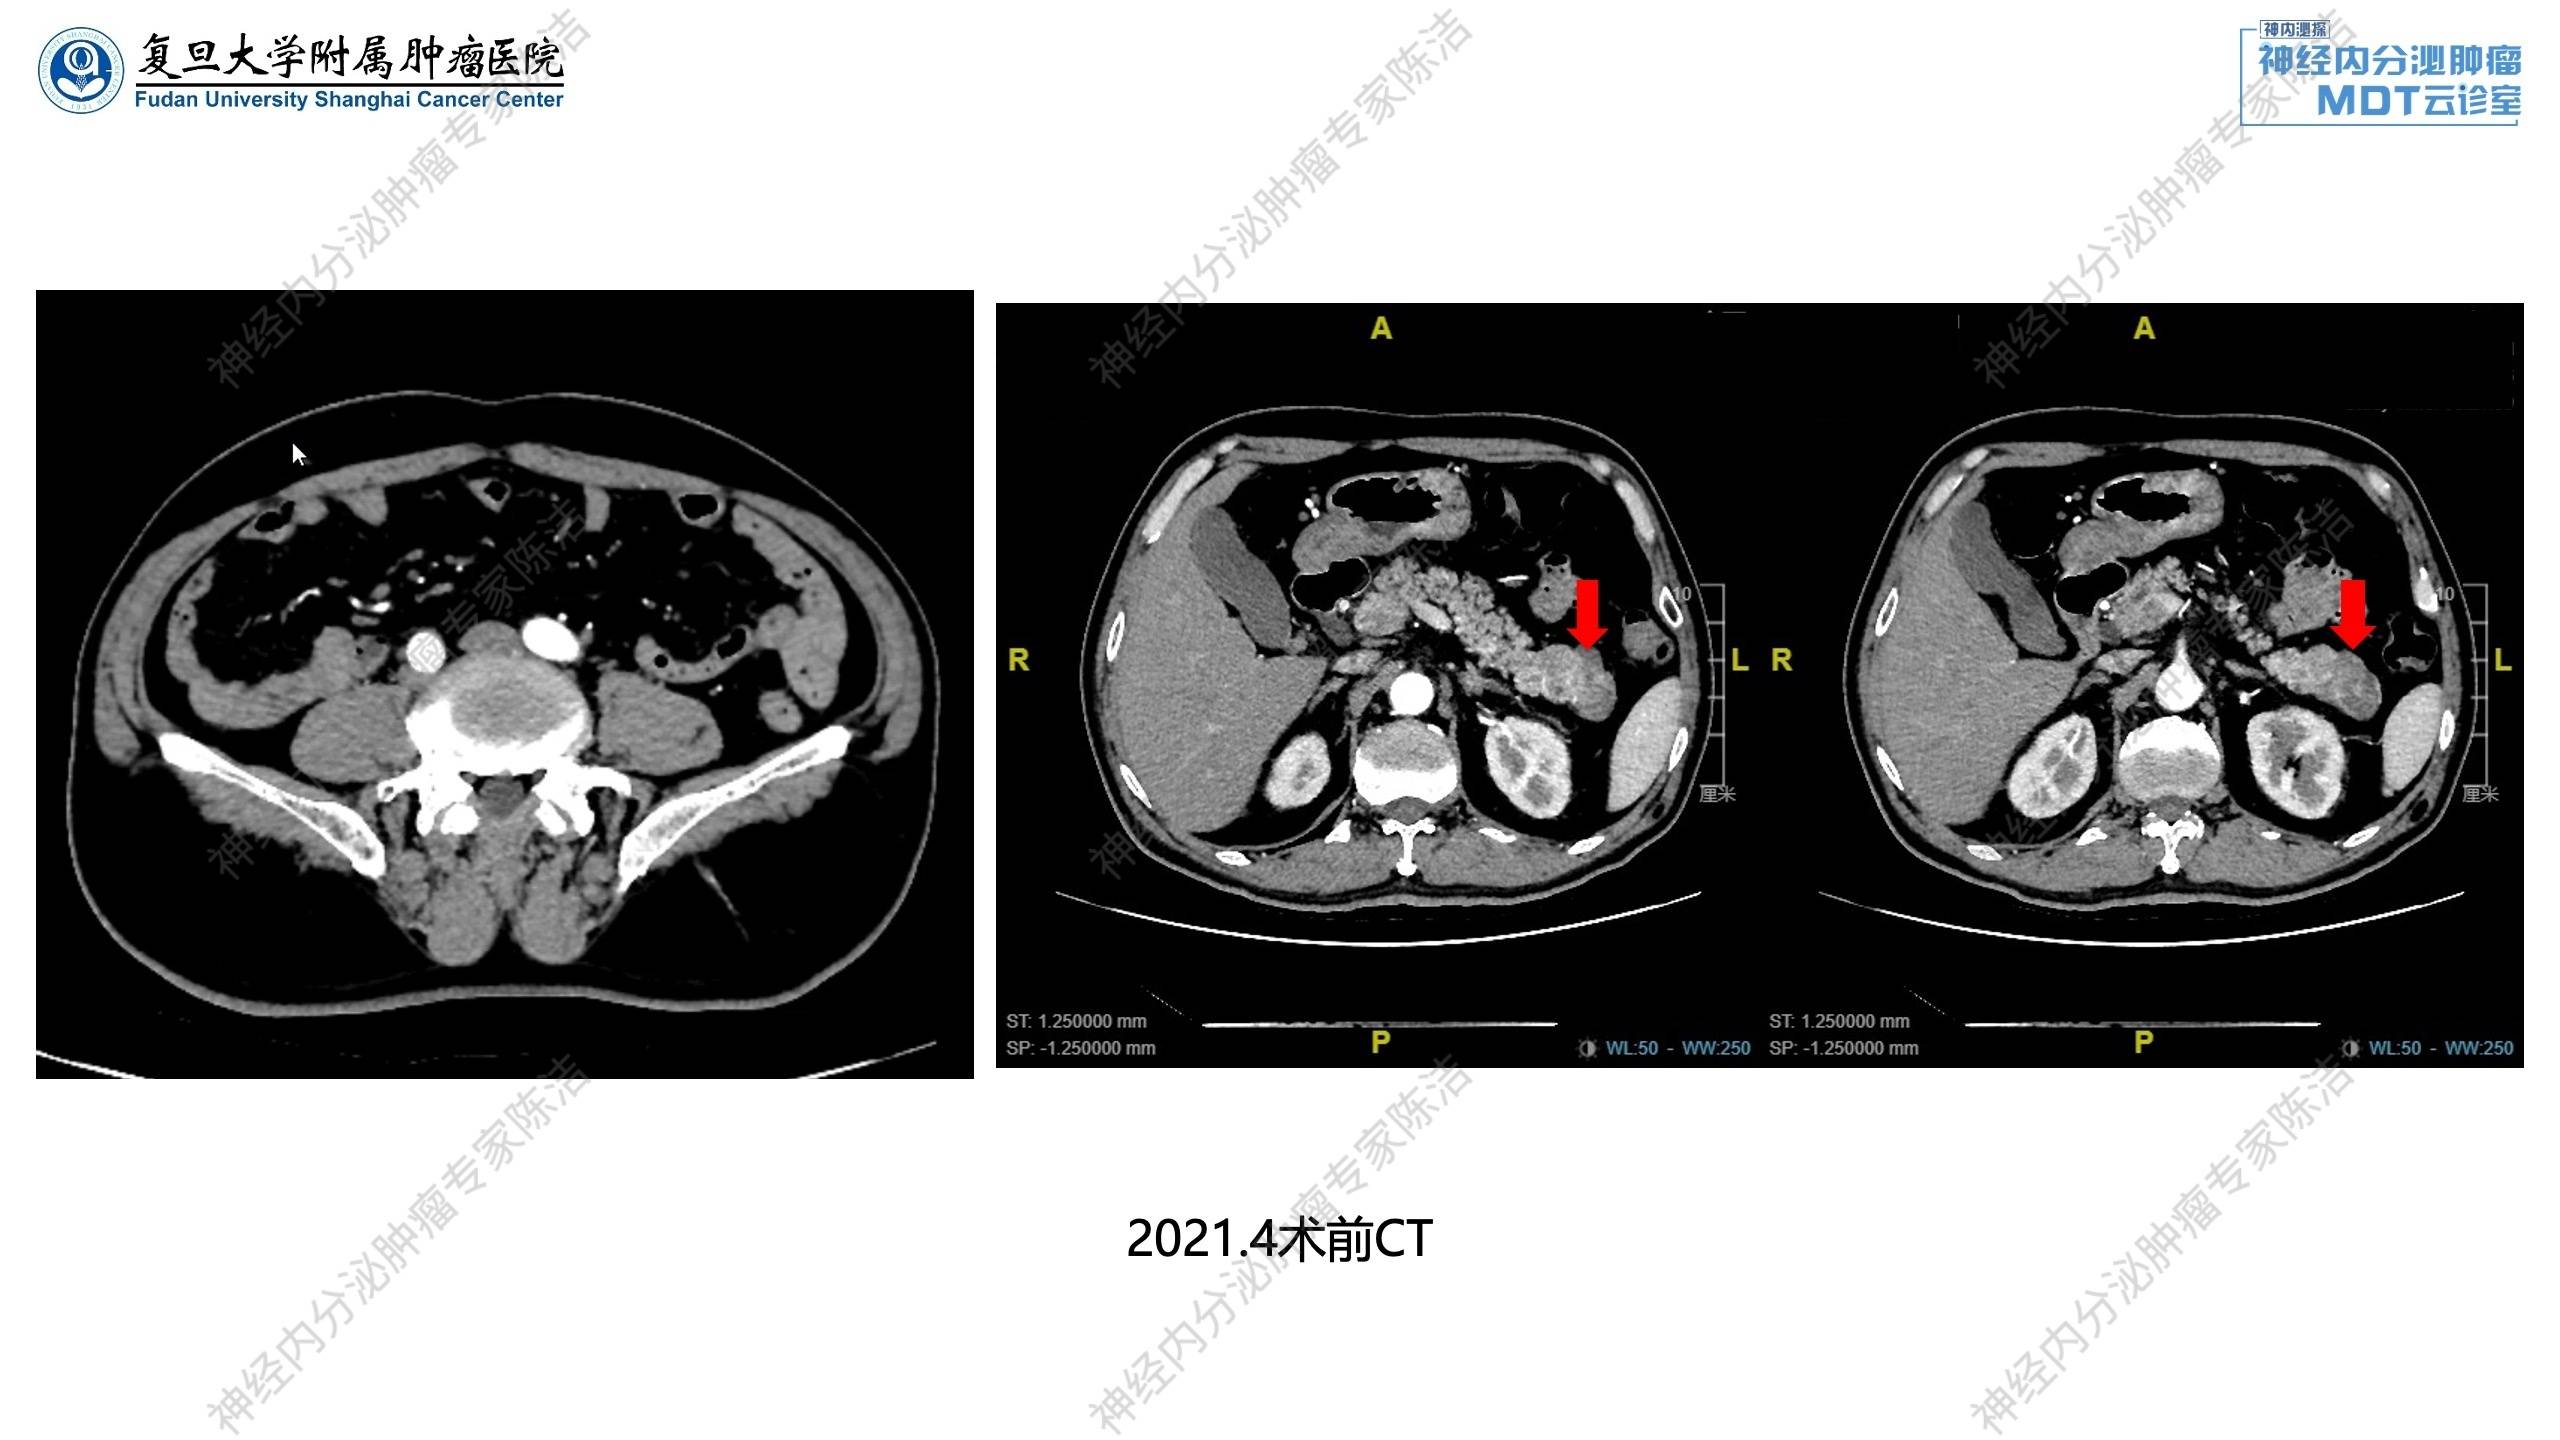

2021年4月:腹部增强CT提示胰尾占位,神经内分泌肿瘤可能,胰管略扩张。

放射诊断科汤伟教授:术前增强CT显示胰尾部有一个明确占位,密度不均匀,富血供伴有低强化区,符合神经内分泌肿瘤特征。在动态图上可以看到肿块旁边还有多个强化的病灶,考虑多发胰腺神经内分泌瘤,提示临床有遗传综合征(如MEN-1综合征)的可能。关于疗效评估,CT动态展示了纵隔淋巴结的变化:2024年5月淋巴结较前明显增大(PD),更换替莫唑胺为基础的化疗方案后,淋巴结明显退缩(PR),证实治疗有效,停替莫唑胺治疗后,多次复查肿瘤稳定。